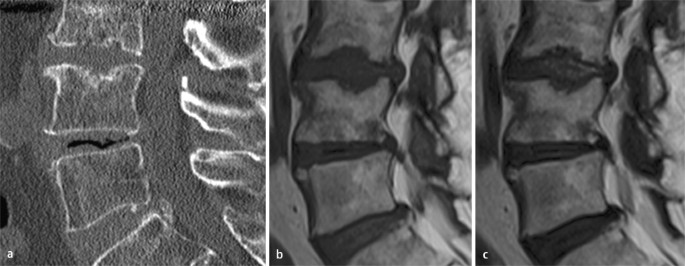

Erosive Osteochondrose